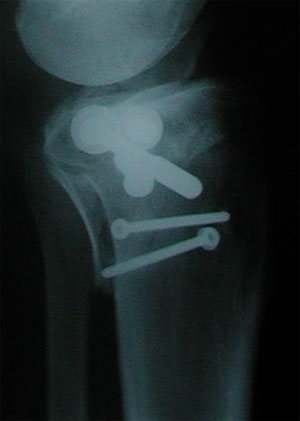

Oben: Röntgenbild vom 24. Oktober; alles klar zum Schrauben entfernen.

Oben: Röntgenbild (Seitenansicht) vom 24. Oktober 2001. Das am linken Rand des Schienbeinkopfs sichtbare, vorstehende Teil ist wieder vollständig eingewachsen. Dazu als Vergleich hier...

... das Röntgenbild vom 7. Juli 2001: Zwischen dem abstehenden, mit der untersten Schraube fixierten Teil und dem Schienbein klafft noch eine deutliche Lücke.